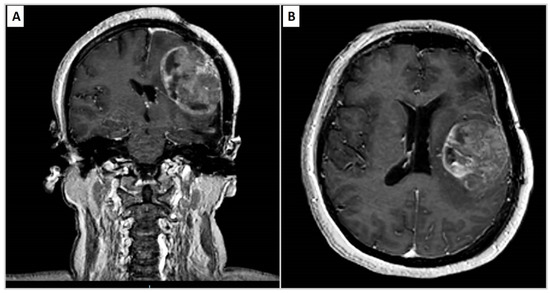

| Years | Symptoms | Diagnosis | Treatment |

|---|---|---|---|

| 2010 | Headache, speech difficulties and hypersomnia | Neoplastic lesion in the left frontparietal area compatible with papillary meningioma | Surgical removal and radiotherapy adjuvant treatment |

| 2015 | Headache | Recurrence of PM | Neurosurgical removal |

| 2020 | Headache, sleep disturbances and functional symptoms | Recurrence of PM | Tumour excision |